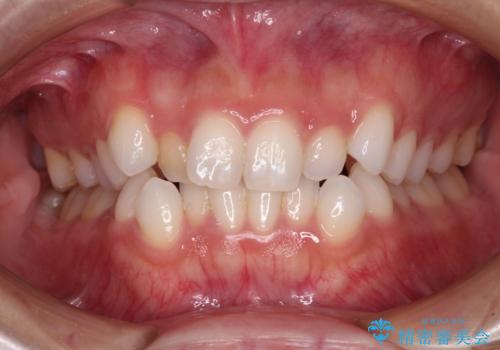

![[マウスピース矯正] 海外留学中でも可能な矯正治療の症例 治療前](https://seimitsushinbi.jp/wp/wp-content/uploads/2025/01/C4-1-500x350.jpg?v=1737343006)